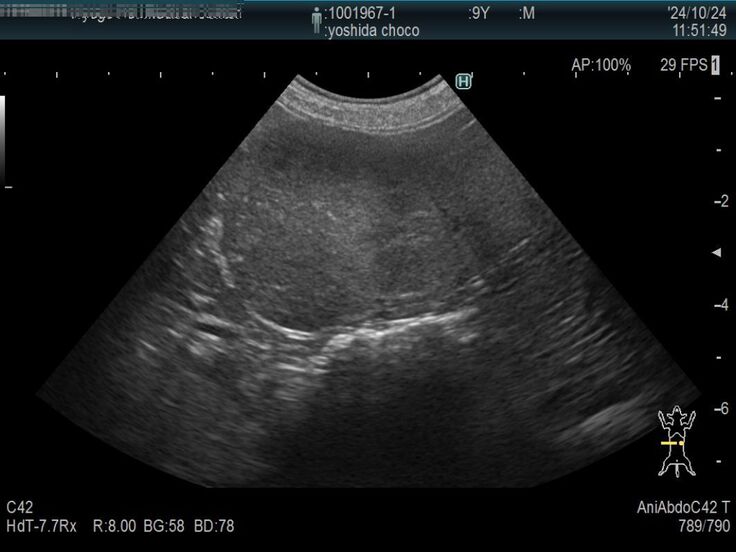

以前より下部尿路疾患で尿路結石を持っているチョコですが、膀胱にある結石が大きくなり膀胱を痛めて膀胱炎を頻繁に発症するようになりました。

膀胱炎から炎症が全身に、更には脾臓の腫瘍が確認されました。

膀胱炎の資料をご覧ください。

検査結果もかなりの異常さが分かると思います。

検査の結果、脾臓肥大が限界近くの爆発寸前になっていることが判明しました。

脾臓は4センチまでなってるから、いつ破裂してもおかしくない状況。